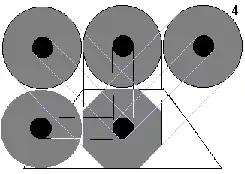

En la figura '4', el ordenador dispone de datos de cuatro incidencias: 45º, 90º, 135º y 180º. Los perfiles de la imagen son ortogonales, lo que la aproximan mucho más a los contornos circulares del objeto real. |